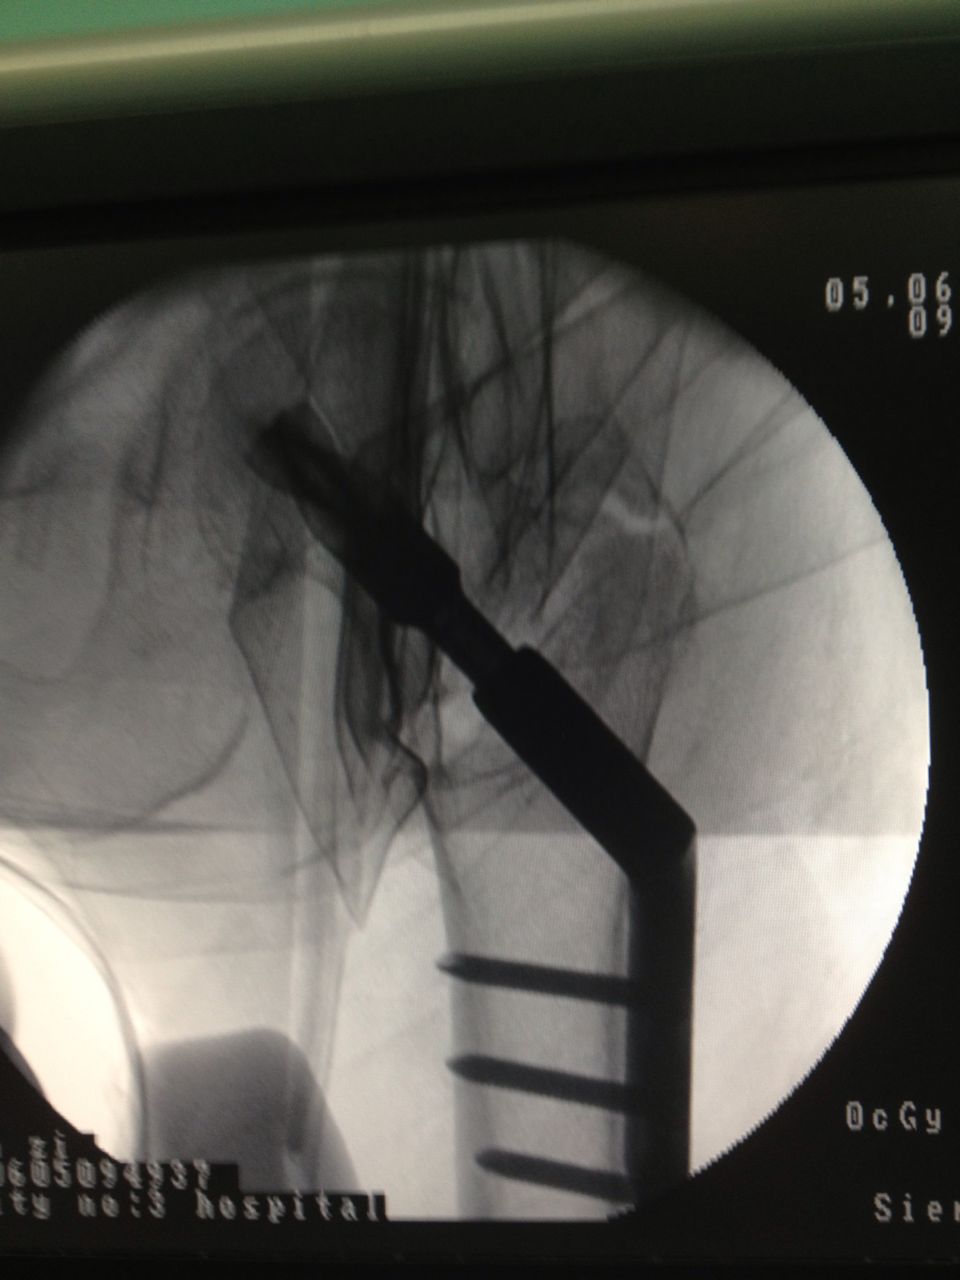

老人应选择何种治疗方案?第三医院骨科、心内科、麻醉科等多科专家组成的专家组认真仔细分析病情,决定采用髋关节微创植入内固定术。6月4日,老人接受手术,在手术牵引床上,通过C臂X光机透视,不切开骨折端闭合牵引复位,在老人骨折处复位到最佳状态时,刘忠国在骨折处开出5公分的口进行螺旋刀片动力髋固定,最大程度减少手术损伤,促进骨折端提早愈合。